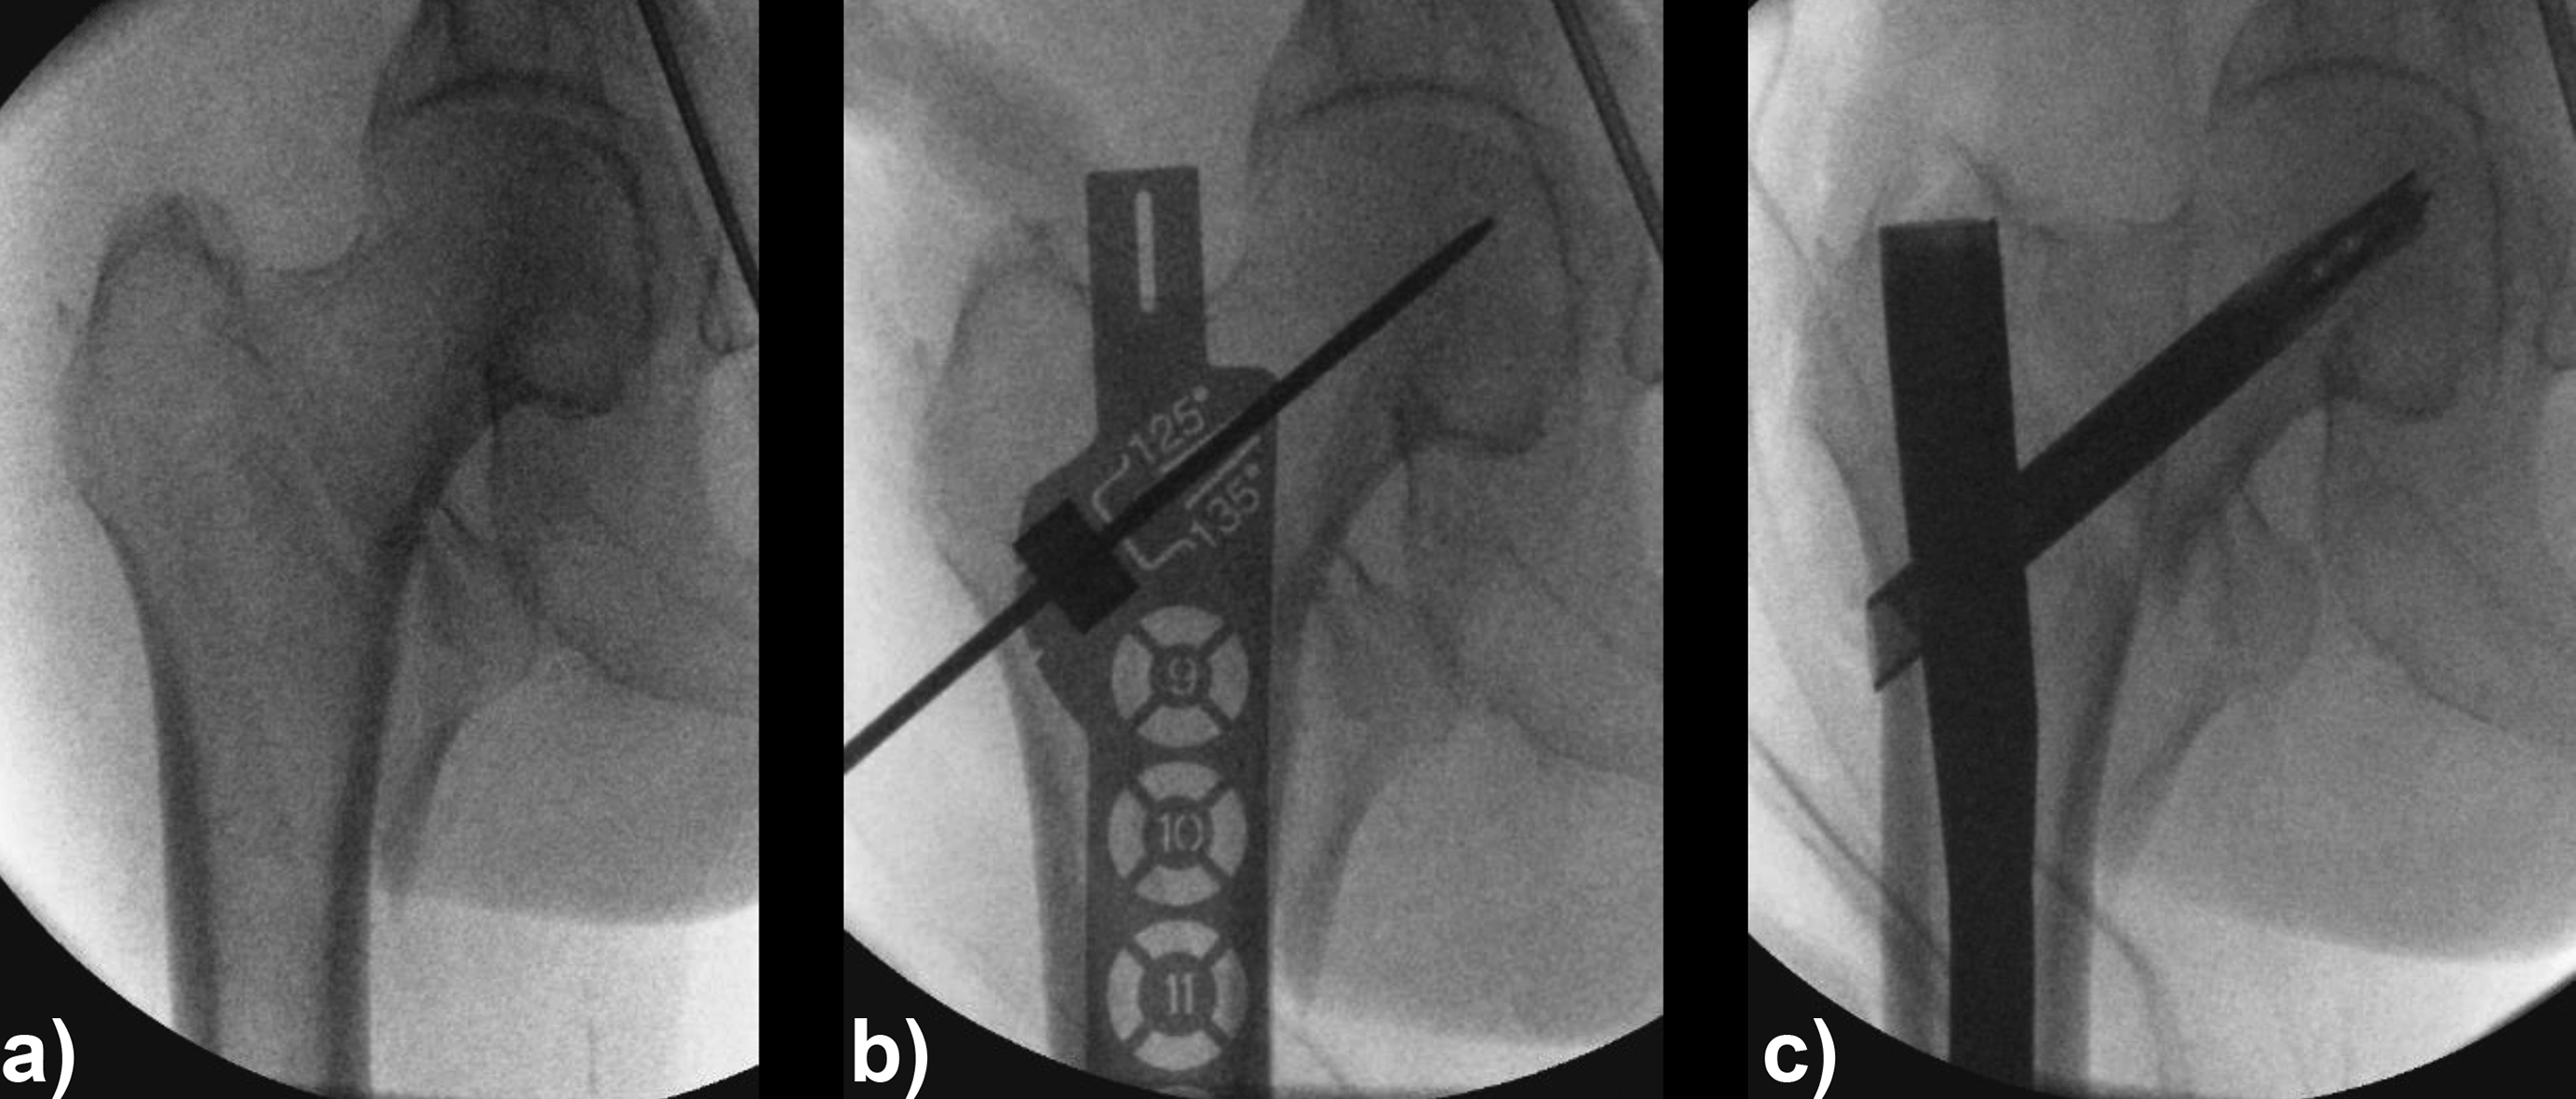

An 83-year-old female patient sustained a 31-A.2.2 fracture of the right proximal femur after a fall at home (Figs 1-2). Intraoperative and postoperative images are shown (Figs 3-5).

Case provided by Michael Blauth, Innsbruck, Austria